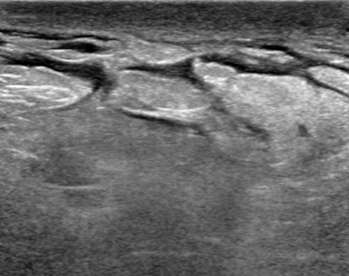

Edema